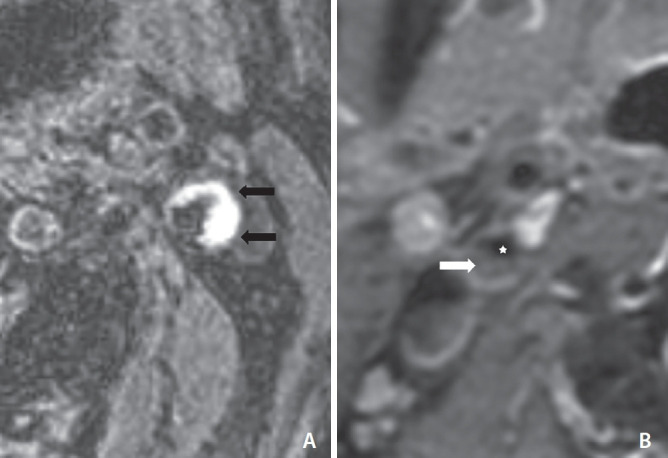

目的:颈动脉斑块的血管壁成像(VWI)能更好地检测不稳定的颈动脉斑块,如斑块内出血(IPH)、富脂坏死核心(LRNC)和薄/破裂的纤维帽。然而,颈动脉支架置入术(CAS)前使用 VWI 的作用尚不明确。因此,本研究旨在确定 CAS 前血管造影和颈动脉 VWI 对无症状颈动脉狭窄的发现,并评估与 CAS 术后临床事件相关的影像学发现:这项回顾性研究纳入了173例连续接受颈动脉VWI、CAS和CAS术后弥散加权成像(DWI)的患者。对颈动脉血管造影(VWI)发现的不稳定斑块和血管造影发现的不稳定斑块进行了分析。我们还分析了CAS术后30天内的临床事件、任何中风、心肌梗死(MI)和死亡的发生率:在173名患者中,101人(58.4%)有初始缺血症状,DWI检查结果呈阳性。有症状的 IPH 患者明显多于无 IPH 患者(62.4% 对 45.8%,P=0.031)。无症状组中狭窄程度、狭窄病变血栓、颈内动脉血流延迟和滤过性血栓阻断血流的发生率明显更高。有 20 名患者(11.6%)在手术后发生了中风、临床症状和/或心肌梗死等临床事件。结论:高脂血症和血管造影显示的腔内血栓是影响CAS术后事件的重要因素:结论:血管造影发现的腔内血栓是影响 CAS 术后临床事件的重要因素。

Results: Of 173 patients, 101 (58.4%) had initial ischemic symptoms and positive findings on DWI. Symptomatic patients were significantly higher in patients with IPH than in patients without IPH (62.4% vs. 45.8%, P=0.031). Degree of stenosis, thrombus of the stenotic lesion, flow delay of internal carotid artery, and flow arrest by filter thrombus had significantly higher prevalence in the symptomatic group. Twenty patients (11.6%) had post-procedural clinical events such as any stroke, clinical symptoms, and/or MI. Hyperlipidemia and intraluminal thrombus on angiography were identified as significant factors influencing post-procedural events after CAS.